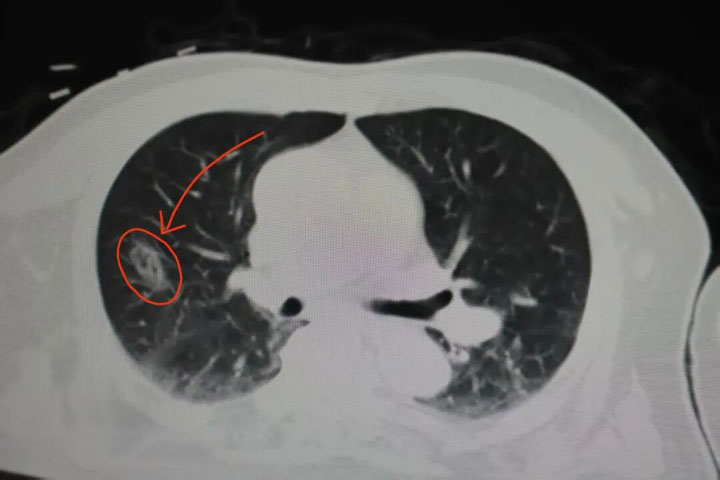

下图可见:术后CT下消融区域正好覆盖结节位置

后续等待自身吸收恢复即可